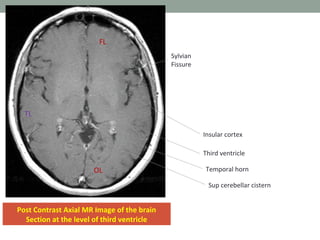

Post Contrast Axial MR Image of the brain

Section at the level of third ventricle

TL

FL

OL

Sylvian

Fissure

Temporal horn

Sup cerebellar cistern

Insular cortex

Third ventricle

Post Contrast AxialMR Image of the brain Section at the level of third ventricle TL FL OL Sylvian Fissure Temporal horn Sup cerebellar cistern Insular cortex Third ventricle